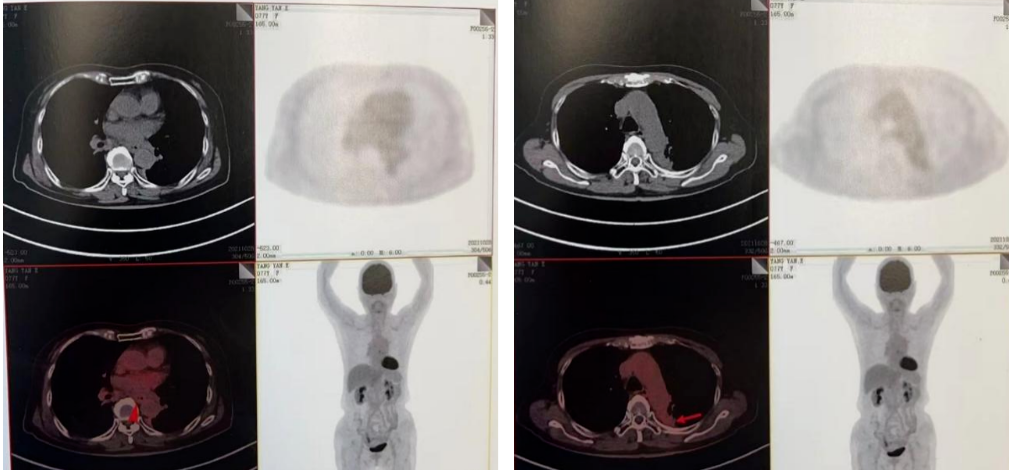

2022-03-28 PET-CT:1、食管癌放化疗后,食管胸中段管壁不规则增厚伴结节状代谢增高,与上次(2021-10-28)PET/CT检查对比,病灶代谢较前明显增高,考虑为肿瘤复发病灶。2、左肺癌放疗后及靶向药治疗后,原左肺上叶团块状高代谢“肿瘤灶”,现范围较前稍缩小,代谢较前稍减低,考虑为治疗后改变(肿瘤完全活性受抑,伴少许炎性反应可能)。

2、左肺腺癌cT3N0M0IIb期综合治疗后

二线治疗

2022年-04-01~2022年08-行化疗+靶向+免疫治疗,具体方案为白蛋白紫杉醇260mg/m2即400mg d1 q3wX6周期;化疗同时行尼妥珠单抗400mg q3w;化疗同期行斯鲁利单抗200mg q3w治疗及维持治疗至今。